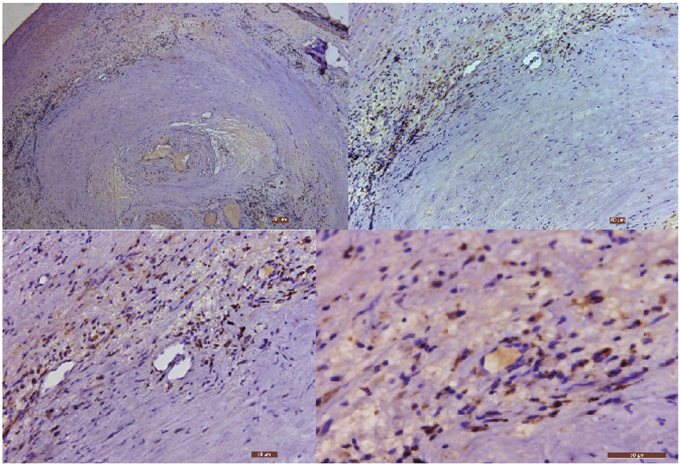

The immunohistochemical analysis of Cpn and CMV in the carotid atherosclerotic plaque of the 25 patients in experimental group: ① the Cpn antigens are shown as brown or coffee granules, and their positive granules are expressed in the cytoplasm and nucleus (Figure 1). ② The location of the positive expression of CMV antigens was similar to that of Cpn, but their positive granules primarily existed in cytoplasm and were expressed in a few nuclei (Figure 2).

Figure 1: The immunohistochemical staining results of Cpn in carotid atherosclerotic plaque (40×, 100×, 200× and 400×, respectively). Low power microscopy illustrates the serious stenosis of arterial lumen with the formation of blood clots. The nuclei stain is blue, and the granules of Cpn antigens are brown or coffee colored.